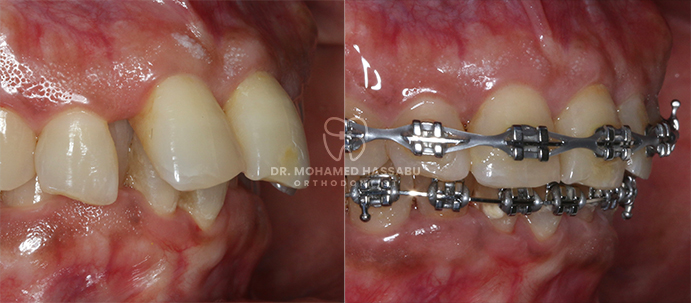

التقويم المعدني عبارة عن أدوات أسنان خاصة مصنوعة من الفولاذ المقاوم للصدأ تساعد في إصلاح الأسنان التي لا يتم محاذاتها بشكل صحيح. تحتوي هذه التقويمات على أقواس معدنية تلتصق بالأسنان وأسلاك رفيعة تعمل على تحريك الأسنان بلطف إلى الأماكن الصحيحة مع مرور الوقت. من خلال ارتداء هذا التقويم، تصبح الأسنان المزدحمة أو الملتوية مستقيمة تدريجيًا، مما يخلق ابتسامة جميلة لك ولطفلك.

لقد كانت التقويمات المعدنية حلاً موثوقًا ومثبتًا لتقويم الأسنان لأجيال عديدة. إنها فعالة للغاية في تصحيح مشاكل الأسنان المختلفة، بما في ذلك الأسنان المزدحمة، والفجوات، والعضة العلوية، والعضة السفلية. من خلال الضغط بلطف على الأسنان مع مرور الوقت، تقوم التقويمات المعدنية بنقلها تدريجياً إلى مواقعها الصحيحة، مما يخلق ابتسامة متناغمة ومتماسكة.

تركيب التقويمات المعدنية:

بفضل الدقة والعناية، سيقوم أخصائيو تقويم الأسنان الكبار لدينا بوضع التقويمات المعدنية بلطف على الأسنان، مما يضمن ملاءمة مريحة.